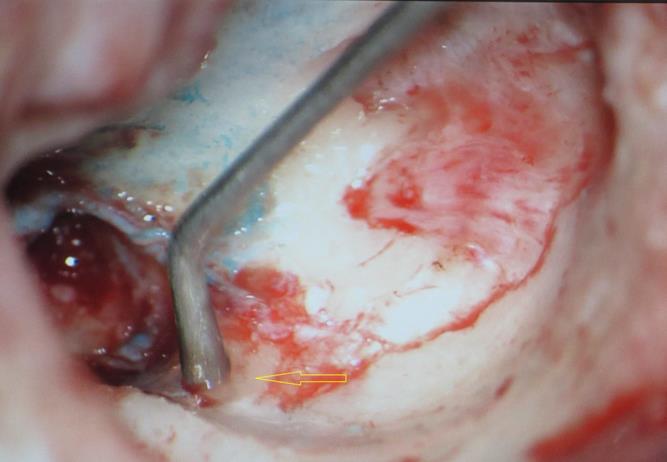

A 13 year old girl presented in ENT outpatient department with complains of recurrent right ear purulent discharge from pre and post auricular area for last 5 years. She had a history of incision and drainage in right post auricular area six months prior for similar complain. On local examination, there was right Grade II8microtia with atretic External Auditory Canal (EAC) and pre-auricular skin tag (Figure 1). A small fistulous opening was also seen in right cavum conchae region. Left ear examination was normal with intact tympanic membrane. Tuning fork tests using 256 and 512 Hz tuning forks showed moderate to severe conductive hearing loss in right ear with Rinne’s test positive in left ear. HRCT scan of temporal bones showed membranous atresia of right EAC with grade II microtia. Soft tissue density was seen filling the EAC and the entire middle ear cavity (Figure 2A). A CT based fistulogram done four months before our consultation identified multiple fistulous tracts situated in post auricular region and anterior to stylomastoid foramen in inframastoid region. These fistulous tracts were communicating through middle ear cavity (Figure 2B). There was associated erosion of posteroinferior and anteroinferior wall of EAC. Ossicles were dysplastic or eroded. Inner ear structures were normal. Patient underwent right radical mastoidectomy with wide conchal meatoplasty under general anaesthesia. Intraoperatively, there was right EAC membranous atresia with fistulous opening in cavum conchae. Cholesteatoma sac was seen filling the mastoid antrum area extending into middle ear cavity and EAC with erosion of posterior canal wall. Except remnant of malleus head which was fixed to epitympanic wall, no other ossicle was found. Oval window area showed bony depression without any overlying stapes footplate (Figure 3). Lateral semicircular canal bulge, facial nerve canal and chorda tympani were found at their usual locations (Figure 4). Obliteration of mastoid cavity posterior to vertical segment of bony facial canal was done using pedicled temporalis muscle flap to reduce the size of postoperative cavity. Middle ear cavity was covered with temporalis fascia graft.

Figure 4.Arrow pointing to exposed facial nerve (vertical segment)

Arrow pointing to exposed facial nerve (vertical segment)